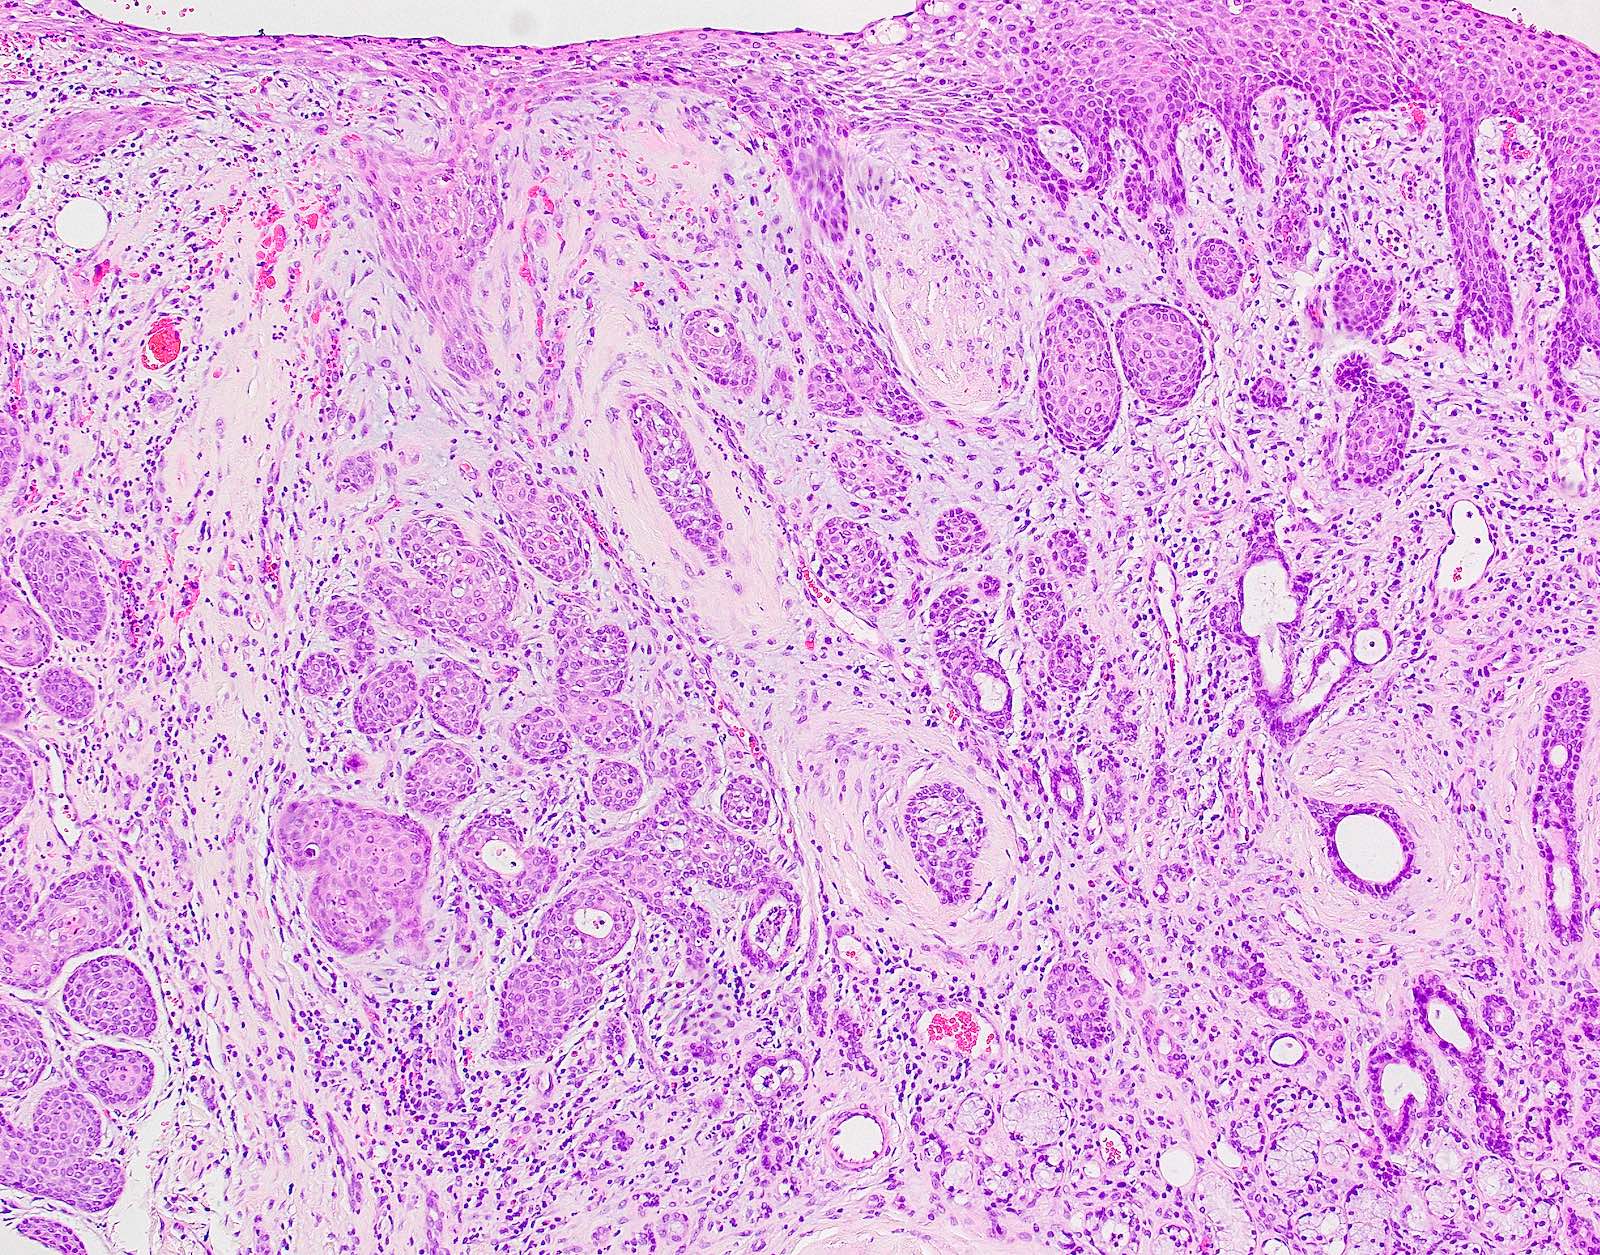

Microscopic (histologic) images

Contributed by Molly Housley Smith, D.M.D.

PEH in granular cell tumor PEH in granular cell tumor

PEH in granular cell tumor

B. Granular cell tumor with overlying pseudoepitheliomatous hyperplasia (PEH). Microscopic sections show a dome shaped mass of pale, basophilic, plump granular cells surfaced by hyperkeratotic and hyperplastic epithelium. Although the rete ridges are significantly proliferative and demonstrate keratin pearls, overt cytologic atypia is not appreciated. This proliferative pattern of the epithelium is termed pseudoepitheliomatous hyperplasia and is known to be associated with granular cell tumors. Answer A is incorrect because although there is a thickened layer of parakeratin, this answer choice ignores the replacement of the fibrous stroma by plump granular cells. Answer C, a common pitfall in the diagnosis of this tumor, is incorrect because although the epithelium is proliferative, prominent cytologic atypia is not appreciated. The pathologist must be keen in recognizing the underlying replacement of the fibrous stroma with plump granular cells and must know that granular cell tumors characteristically show PEH in many cases. Answer D is incorrect because verrucous carcinoma would show keratin clefting and prominent, bulbous, plunging rete ridges that push into the underlying muscle.